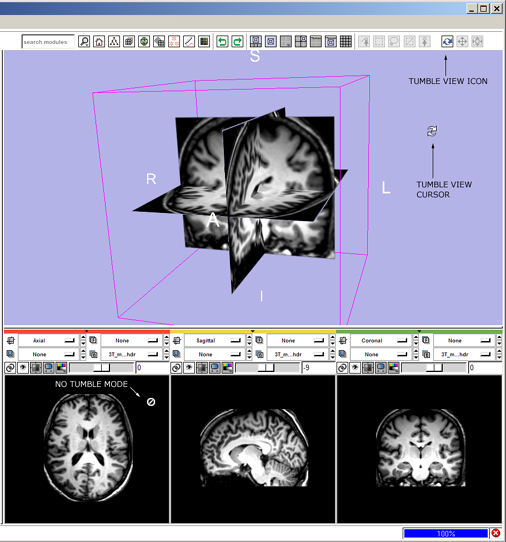

Simple workflow storyboard

Below is how a user would use the mouse-mode interface to tumble, track and dolly the camera to get the 3D View to look the way they like, and then put down three fiducial points and adjust their position.

1(novice) tumble: click the view tumble mouse-mode icon

- --> mouse-tumble icon highlights and all others deselect, cursor changes to indicate mouse-tumble mode.

- then left-Click and drag in the 3D Viewer to rotate the view,

1(expert) tumble: ctrl+left-Click and drag in the 3D Viewer,

- --> mouse-tumble icon highlights and all others deselect; cursor changes to indicate mouse-tumble mode; view tumbles.